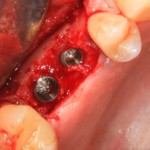

Рисунок 43, 44, 45. Установка имплантов одномоментно с операцией синуслифтинга: слева – этап синуслифтинга, в центре – подготовка лунки под имплантат (виден спейсер и слизистая оболочка гайморовой пазухи), справа – установленный имплант

Оптимальное расстояние от дна гайморовой пазухи до верхней точки альвеолярного гребня верхней челюсти, при котором возможна стабилизация импланта длиной 10-11 мм – не менее 3-4 мм. Однако, в некоторых случаях имплантат длиной 11 мм удается стабилизировать в меньшем объеме костной ткани (рис 46, 47, 48):

Рисунок 46, 47, 48. Стабилизация импланта при толщине костной ткани менее 3 мм: слева – установка импланта после синуслифтинга, в центре – заполнение субантрального пространства спейсером, справа – рентгенологический контроль.